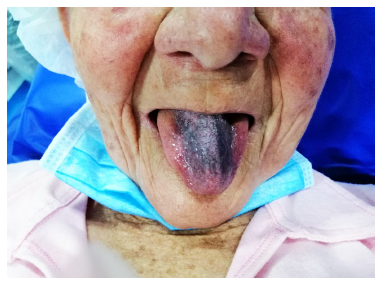

Durante la endoscopia se encuentra lengua de coloración oscura negruzca en su dorso, con aspecto de “pelos”, sin compromiso en los bordes ni en la punta, con zona de despigmentación blanquecina en la zona central posterior (Figuras 1 y 2). En el esófago medio (25 cm), por paredes laterales derecha, izquierda y anterior, hay lesión nodular, infiltrante y friable que produce estenosis franqueable de 12 mm y llega hasta los 30 cm, sin compromiso esofágico distal (Figuras 3 y 4).

Figura 1 Paciente con coloración negra del dorso de la lengua, que no compromete los bordes laterales ni la punta.

La lengua negra pilosa (LNP) es una condición benigna que consiste en el oscurecimiento y apariencia velluda (“peluda”) del dorso de la lengua, descrita por primera vez por Amatus Lusitanus en 1597 7,8. Su prevalencia es variable, aunque en estudios de salud oral es tan alta como del 11,3%, más común en hombres de la tercera edad, fumadores severos, consumidores de té negro y café 9,10, VIH positivos, edéntulos, con cáncer de próstata o linfoma de células B 6, y en los pacientes en tratamiento con antibióticos 2-4. Clínicamente se observa una placa o membrana negra distribuida en el dorso de la lengua, sin compromiso lateral ni de su punta (Figura 1) y, como en este caso, sin compromiso en la parte central y posterior (Figura 2). El cambio de color más común es negro, pero varía a café, verde o amarillo 11.